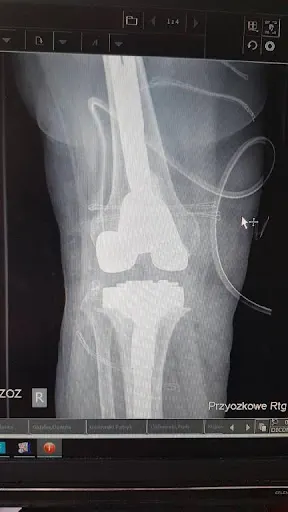

W Gdyni, przy ulicy Przebendowskich 40/2, prowadzi gabinet ortopedyczny dr Emil Zyzik. Specjalista ten cieszy się doskonałą reputacją wśród pacjentów – na Google jego ocena wynosi 5.0 na 5 gwiazdek na podstawie sześciu opinii. To miejsce, gdzie mieszkańcy Trójmiasta mogą liczyć na profesjonalną opiekę w zakresie ortopedii, zlokalizowane w dogodnym punkcie dzielnicy o kodzie pocztowym 81-543. Pacjenci chwalą dr. Zyzika za indywidualne podejście do każdego przypadku. Jeden z nich relacjonuje, że od czasów liceum zmagał się z problemem kolana, ale po konsultacji, badaniu i wstrzyknięciu kwasu hialuronowego zauważył wyraźną poprawę. Inny podkreśla dokładność odpowiedzi na wszystkie pytania oraz fakt, że lekarz poświęca pacjentowi tyle czasu, ile potrzeba, unikając pośpiechu typowego dla masowych wizyt. Takie opinie wskazują na skrupulatność i zaangażowanie w codziennej praktyce. Gabinet dr. Emila Zyzika to solidny wybór dla osób szukających rzetelnej pomocy ortopedycznej w Gdyni. Wysoka średnia ocen potwierdza zaufanie lokalnej społeczności, a pozytywne doświadczenia pacjentów mówią same za siebie. (Liczba słów: 198)